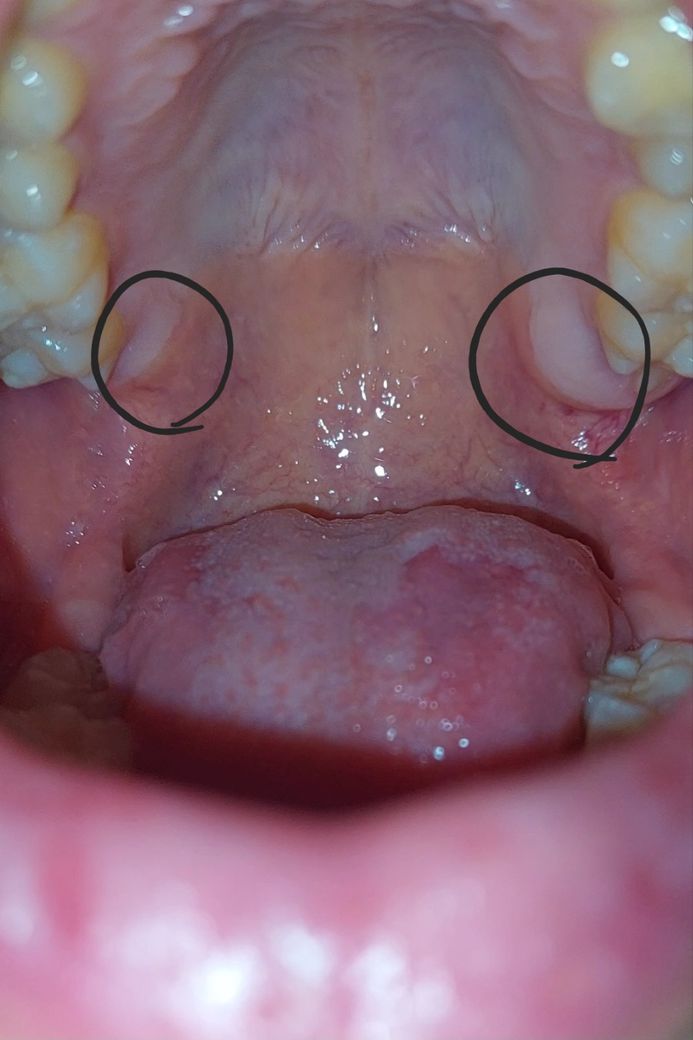

입천장에 하얗고 단단한 부분이 대체 뭘까요?

입안을 거울로 들여다보다가 발견했는데 양쪽 크기가 다르고 만지면 단단한 느낌이 듭니다. 이게 뭘까요? 병원에 가야 한다면 치과를 가봐야 할까요?

사랑니가 없다면 잇몸뼈가 저렇게 보이는거 같습니다. 크게 문제가 잇는건 아니니 걱정하지 않으셔도 될것같습니다.

해당 부위의 해부학적 명칭은 상악결절이고 위 턱 사랑니가 위치한 부분입니다. 보통 사랑니가 잇몸, 잇몸뼈 속에 있고 맹출을 시작할 때 맹출성 치은염을 유발하여 잇몸 부위가 살짝 자극이 가해지는 경우가 있습니다. 치과에서 해당 부위 방사선 사진을 찍어보시고 사랑니 유무를 검사해보시고 그 다음에 사랑니와 상관이 없다는 것으로 판명되면 구강내과가 진료과로 있는 치과를 한번 가보시는 것이 좋을 것 같습니다.

해당 부위는 시야를 지탱하는 치조골이 밖으로 자라서 나와 있는 형태입니다 큰 문제가 있는 것은 아니기 때문에 걱정하지 않으셔도 되지만 딱딱한 음식을 먹었을 경우에 해당 부위에 상처가 나서 불편할 수 있기 때문에 너무 딱딱하거나 날카로운 음식을 먹지 않는 것이 좋습니다